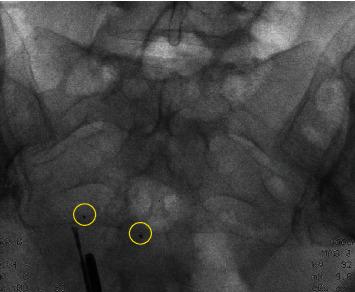

We present a case about Essure removal surgery in which the third markers of the device have torn off. The woman needed a second surgery for complete removal of the devices. Fluoroscopy during surgery is a good method to visualize the lost fragments. With fluoroscopy, a hysterectomy is not needed for complete removal. It is important to understand the structure of the device and to be aware of the four radiopaque markers during surgery and their removal.

我们介绍了一例关于取出Essure装置的手术病例,该装置的第三个标记物已脱落。该女性需要进行第二次手术以完全取出该装置。手术中的荧光透视是可视化丢失碎片的好方法。借助荧光透视,无需进行子宫切除术即可完全取出。了解该装置的结构并在手术过程中知晓四个不透射线的标记物及其取出情况非常重要。